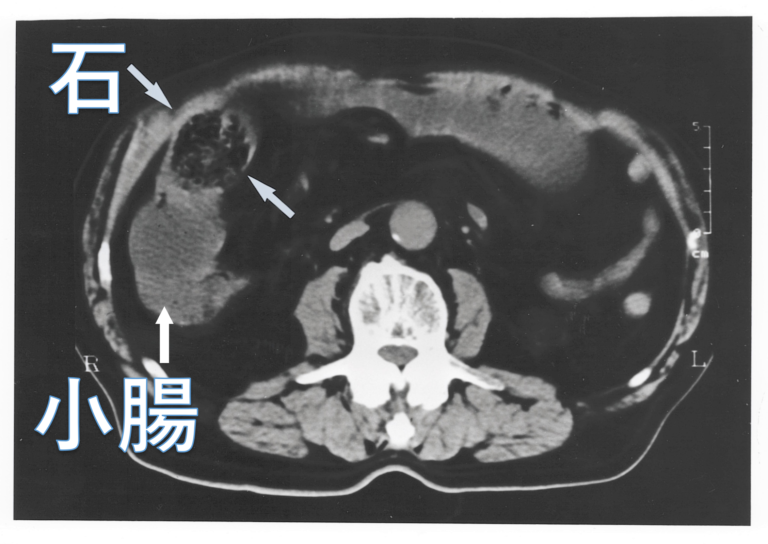

柿の美味しい季節です私は柿が大好物ですが一つだけご注意「空腹時」に柿を食べると「柿胃症」を起こす場合があります胃石の形成で激痛を伴い死に至る場合もあり祖母はこの病で急死しました体質もあり必ず発症するわけではないが「空腹時に柿だけ大量に食す」...